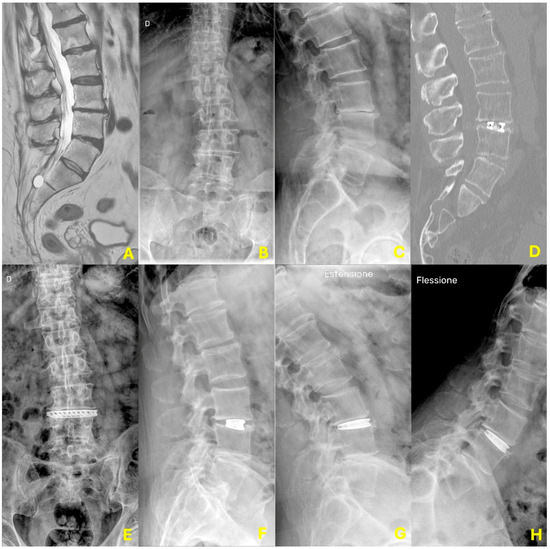

3.4. Radiographic Results

| Radiographic Measure | Baseline | 1 Month Post-Op | 6 Months Post-Op | 1 Year Post-Op | Change from Baseline at 1 Yr |

|---|---|---|---|---|---|

| Mean Disc Height (mm) | 6.37 ± 1.34 | 10.04 ± 1.34 ** | 9.65 ± 1.18 | 9.33 ± 1.21 | Significant * |

| Mean Segmental Lordosis L3-L4 (°) | 6.67 ± 1.63 | 10.69 ± 1.79 ** | 10.04 ± 1.37 | 9.88 ± 1.36 | Significant * |

| Mean Global Lumbar Lordosis (°) | 57.25 ± 7.31 | 60.27 ± 5.5 ^ | 61.31 ± 4.83 | 60.76 ± 4.63 | Significant * |

| Fusion Rate (at 1 year) | N/A | N/A | N/A | 97.9% (48/49) | N/A |